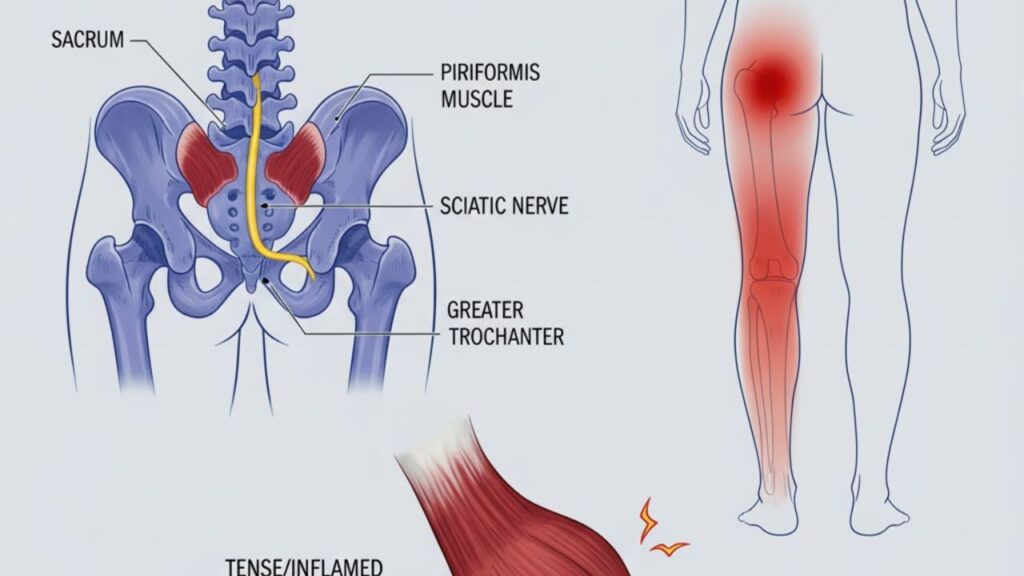

Na maioria dos casos, o tratamento conservador é eficaz para controlar os sintomas. Isso inclui um programa de fisioterapia com foco em alongamentos específicos para o músculo piriforme e fortalecimento da musculatura do quadril e core, além do uso de medicamentos anti-inflamatórios e relaxantes musculares para o controle da dor e do espasmo.

Quando o tratamento conservador não é suficiente para aliviar a dor, o ortopedista pode indicar infiltrações. Realizadas com precisão através da guia de ultrassom, a aplicação de anestésicos e corticoides diretamente no músculo piriforme ajuda a reduzir a inflamação e a quebrar o ciclo de dor e espasmo, proporcionando um alívio mais rápido e duradouro.

A cirurgia é uma opção rara, indicada apenas para os casos mais graves e refratários, que não respondem a nenhum outro tipo de tratamento. O procedimento consiste na liberação cirúrgica do músculo piriforme para descomprimir o nervo ciático, aliviando a pressão de forma definitiva.